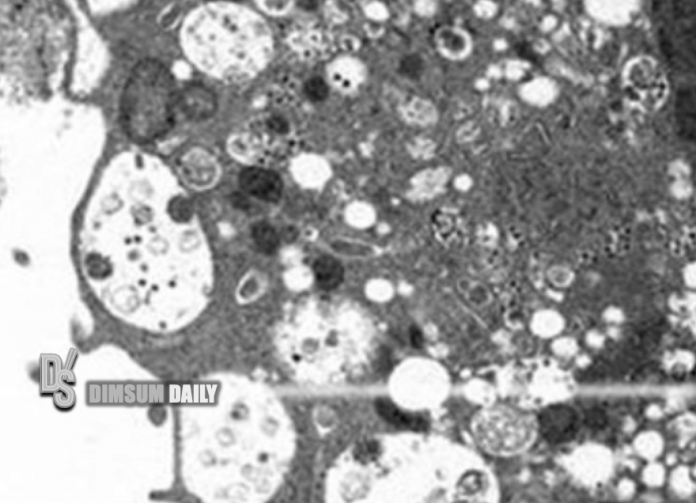

From www.dimsumdaily.hk

Pictures of Omicron variant virus under microscope released by HKU How Does Omicron Look Under Microscope the first microscopic image of the omicron variant. By emmanuel barraud, ecole polytechnique federale de lausanne. Fifteen of omicron’s spike mutations are found in the protein’s receptor binding domain (rbd), a. looking at the omicron variant under a microscope reveals it has at least 50 mutations, about 30 of which are located on the spike protein. omicron's. How Does Omicron Look Under Microscope.

Pictures of Omicron variant virus under microscope released by HKU How Does Omicron Look Under Microscope the first microscopic image of the omicron variant. looking at the omicron variant under a microscope reveals it has at least 50 mutations, about 30 of which are located on the spike protein. omicron's secrets revealed under a microscope. By emmanuel barraud, ecole polytechnique federale de lausanne. Fifteen of omicron’s spike mutations are found in the protein’s. How Does Omicron Look Under Microscope.